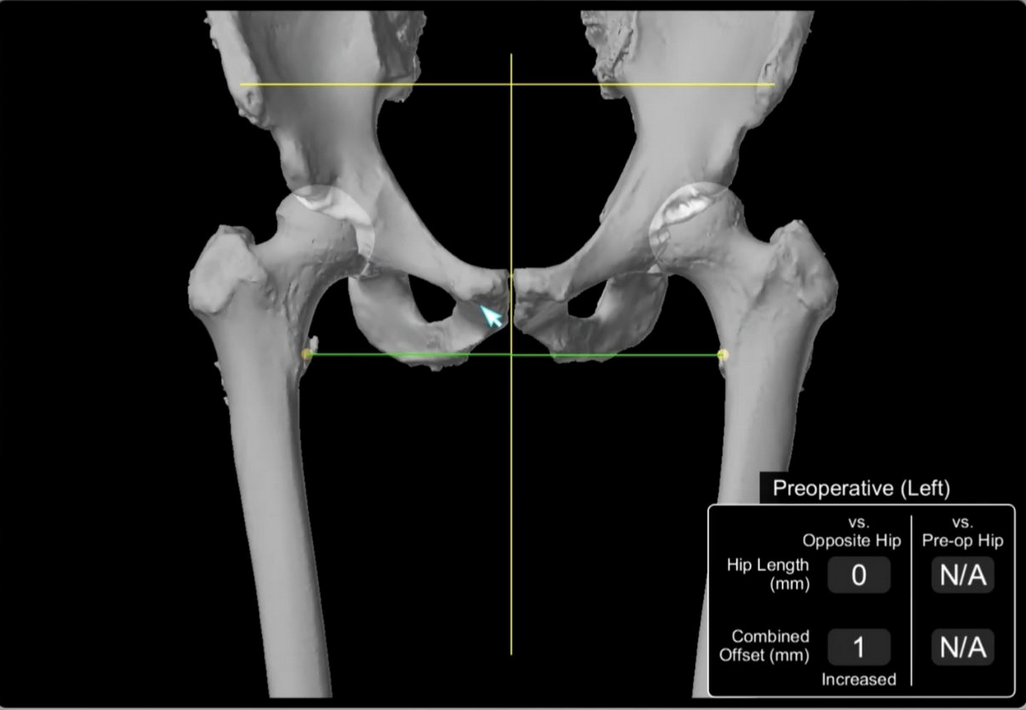

2.  3D CT scan preoperative templaing

Stryker CT

Stryker CT preoperative templating - compares offset from midline NOT femoral offset

5. Computer navigation

stryker CT navigation

Stryker Mako Robot Navigation